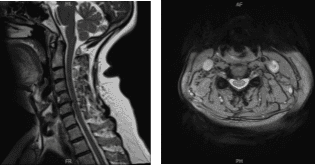

El paciente presentó resultados para la resonancia magnética en la columna cervical y mostró hernias discales posteroventrales en C4-C5 y C6-C7, que hendieran el saco tecal ventral y la superficie de la médula ventral. Bulto anular/espolón vertebral en C5-C6, asociado a espolón bilateral uncovertebral, ligeramente mayor en el lado derecho.

Los hallazgos resultan en un efecto masivo sobre el saco tecal y la médula espinal, una invasión foraminal bilateral y un ligero empeoramiento en la derecha. Estenosis cervical espinal leve. Artropatía facetaria en la región cervical superior, más marcada en la izquierda.

Resonancia magnética de columna cervical sin contraste